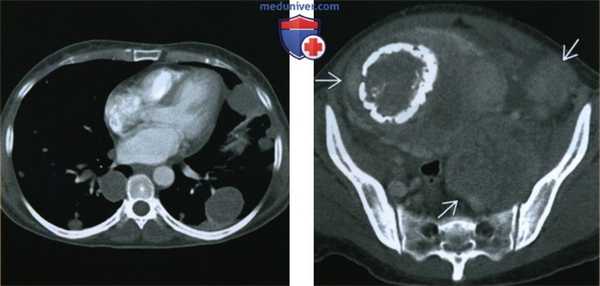

(Слева) Рентгенограмма грудной клетки в заднепередней проекции пациентки 52 лет, которая 15 лет назад подверглась гистерэктомии по поводу миомы матки: множественные узелки различных размеров в обоих легких.

(Справа) При КТ с контрастным усилением в аксиальной плоскости (легочное окно) у той же пациентки в обоих легких видны множественные солидные узелки различных размеров с четкими границами. (Слева) При КТ с контрастным усилением в аксиальной плоскости у той же пациентки в обоих легких видны многочисленные солидные узелки с четкими границами. Узелки имеют однородную структуру, по рентгеновской плотности соответствуют мягким тканям и слабо накапливают контрастное вещество.

(Справа) При КТ с контрастным усилением в аксиальной плоскости у той же пациентки видны множественные мягкотканные объемные образования в малом тазу. При биопсии узелков, расположенных в малом тазу и в легких, оказалось, что они состоят из гладкомышечных клеток без признаков атипии и соответствуют по строению миоме матки.

(Слева) При КТ с контрастным усилением в аксиальной плоскости у той же пациентки в обоих легких видны многочисленные солидные узелки с четкими границами. Узелки имеют однородную структуру, по рентгеновской плотности соответствуют мягким тканям и слабо накапливают контрастное вещество.